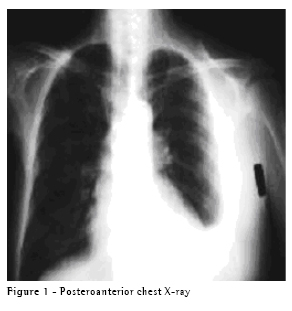

In the assessment, we found vocal fremitus, decreased breath sounds over the left lung and no signs of cardiac decompensation. The chest X-ray revealed moderate left pleural effusion, with no alterations in the mediastinum (Figure 1). The patient was submitted to thoracentesis for symptom relief and for diagnostic purposes.